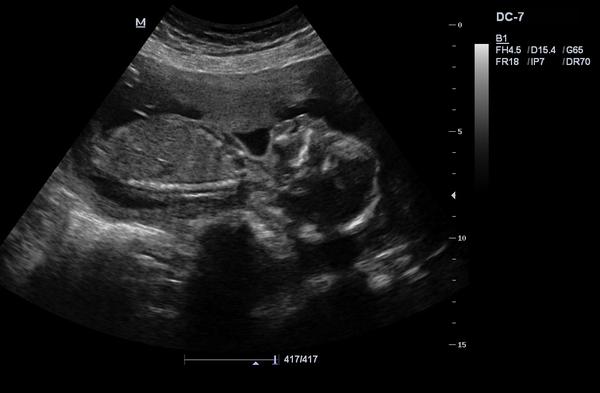

dá se prosím rozpoznat pohlaví?

Pokud ano, tak co myslíte?

bohužel nedá. ☹